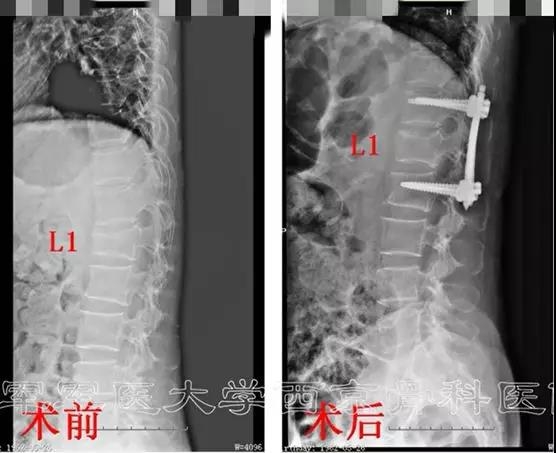

微创导航下单平面螺钉系统腰椎骨折复位内固定术

患者:张某,女,56岁

主诉:高处坠落,腰背部疼痛7小时。

既往史:平车推入病房,强迫体位。腰1椎体棘突压痛+,叩击痛+,双下肢及肛周、会阴区皮肤感觉正常。双下肢肌力正常。双侧膝腱反射、跟腱反射正常。病理反射未引出。

诊断:腰1椎体压缩性骨折

术前X线正侧位片

术后X线片正侧位及三维CT